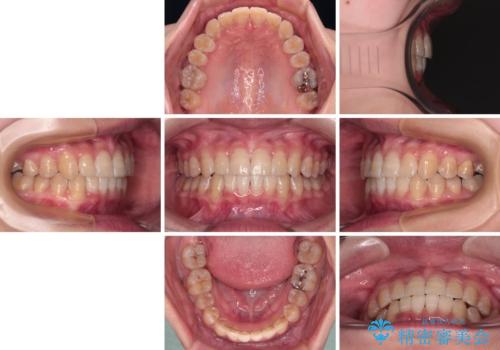

下顎前歯のデコボコが集中しており、奥歯の咬み合わせは、上顎に対して下顎が前方位にある状態でした。下顎の歯列を後方へ移動させる治療はインビザラインの得意とするところですので、1年程度で無事に治療を終えることができました。